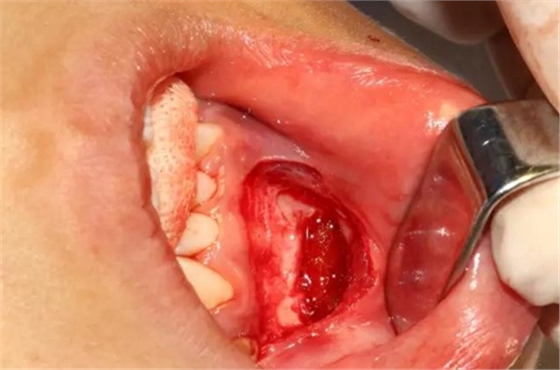

為了減少骨創(chuàng),“T”型分割牙冠

去除冠部